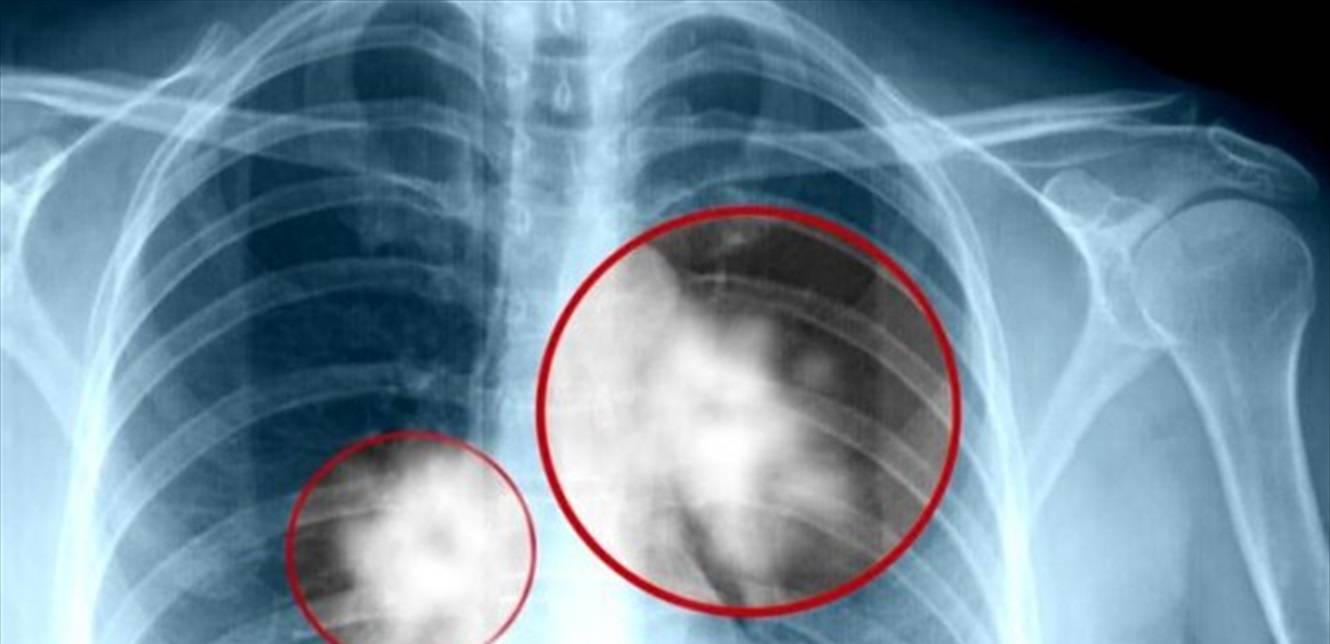

سرطان الرئة.. دراسة حديثة تسلط الضوء